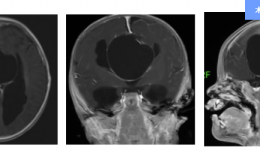

“周主任,这是我家宝宝近况的视频......恢复得特别好!真心感谢医院多学科专家和医护团队的帮助。”近日,茂名市人民医院神经外科三区主任周向阳博士团队收到了患儿家长发来一段视频,视频里的宝宝十分可爱、健康,难以想象在一个多月前他曾患过一...

我院是国家卫健委脑卒中高危人群筛查与干预项目基地,并先后建成国家高级卒中中心以及国家卫生健康委神经介入建设中心,医院神经内科、神经外科、神经重症医学科技术力量雄厚,是医院的“明星专科”团体。其中,神经内科是广东省重点临床专科、2020...